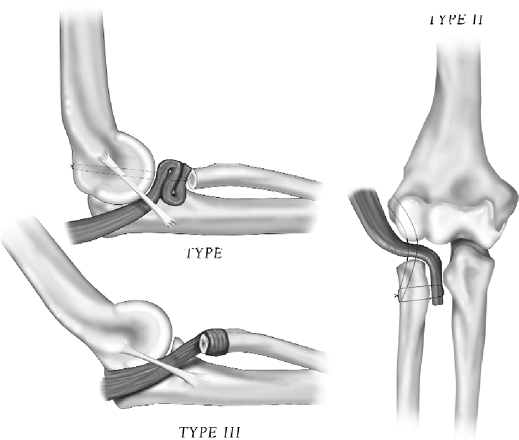

Several variations of the interposition have been used

and are classified as follows: type I, radiohumeral “roll-up”

interposition; type II, radiohumeral/radioulnar interposition; type

III, proximal radial “wrap” (Fig. 23-2). The

specific pathoanatomy determines which of the three types of

interposition is appropriate. The method of harvest is common for all

these applications.

Figure 23-2.

Variations of anconeus rotation/interposition arthroplasty: type I, radiohumeral; type II, radiohumeral/radioulnar; type III, radial “wrap.” |